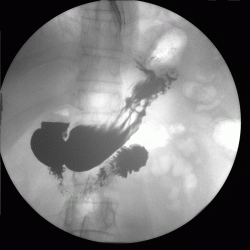

пациента беспокоят боли в области эпигастрия.Выполнена ФГДС вот результат. Пищевод свободно проходим с нормальным просветом и слизистой. Розетка кардии эластиная, смыкается не полностью. В желудке умеренное количество жидкости и слизи с примесью желчи. Слизистая оболочка розовая, отечна, складки нормальной ориентации, утолщены, извиты, эластичность стенок желудка и перистальтика сохранены во всех отделах. В ср/3 тела желудка, на задней стенке определяется язвенный дефект 1,5*0,8 см округлой формы, с припднятыми отечными краями, с конвергенцией складок слизистой, в дне фибрин. Окружающая слизистая отечна, разрыхлена,застойна. При щипковой биопсии подслиистый слой плотный. Антральный отдел, привртаник, луковица и постбульбарный отдел ДПК без особенностей.

ЗАКЛЮЧЕНИЕ: Гипертрофический гастрит. Язва ср/3 тела желудка, maligna ?

Взяли биопсию : покровно-ямочный эпителий без атипии.

Назначено лечение. Контрольная ФГДС- положительная динамика . Размеры язвы 1х0,7 см.

Ну и на последок дообследован рентгенскопически.

По поводу самого обследования. Контраст в нашей клинике- "Бар Випс", ну а газообразующая смесь, как обычно , сода+лимонная кислота.

А сама методика как везде. Исследование выполнено на аппарате США фирмы"general electric" presicion.

Может,все-таки учитывая подозрение специалиста ФГС на малигнизацию, и был направлен в рентгенкабинет.Все же оценить перистальтику,наличие ригидных участков ,считаю, можно лучше с помощью R-скопии. А как известно ригидность -один из признаков злокачественности.

3.Вы совершенно правы по поводу рентгенологического исследования (перистальтики, ригидности и пр.). Должен отметить, как это не прозвучит парадоксально, что 20 лет тому, когда рентгенологические исследование все еще оставалось ведущим исследованием в гастроэктерологии (хотя эндоскопия уже была и "набирала силу"), мы исследовали пациентов более тщательно, используя максимум возможностей от данного исследования, которое и теперь может дать "фору" многим конкурирующим исследованиям. Но многое забыто или не используется. Совершенно забыта (или не используется?) фармакодиагностика, применение которой, в своё время решало многие диагностические вопросы, да и многое другое...

Уважаемая Людмила Александровна! Классика жанра! Все рентгенологические симптомы язвы желудка налицо!